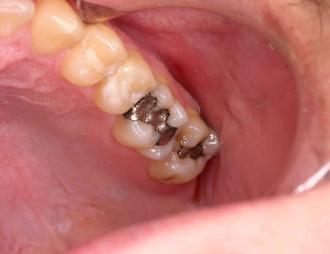

The patient below has 2 defective, decayed amalgam fillings.  We removed the decayed amalgams

and placed white bonded composite fillings.